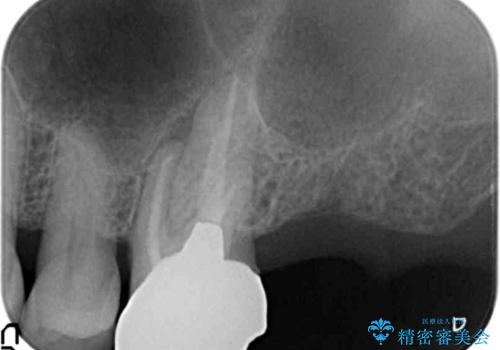

奥歯(左上7)のメタルインレー(銀の詰め物)を除去し精査したところ、奥歯はわれていました。

根尖近くまで深くヒビが入っており保存不可能な状態でした。

患者様のご希望により抜歯してインプラントによる治療を行いました。

上顎洞が近接しており上顎骨の厚みが薄いことから、ソケットリフト(上顎洞底挙上術)をインプラント埋入と同時に行いました。

初診時から治療終了時までのレントゲンをお見せして説明差し上げたところ、「お~!骨ができている!」と喜んで下さいました。

ソケットリフトにより上顎洞底を挙上し骨造成することにより、骨の厚みが薄い部分でもインプラントが可能になります。

インプラントの種類:ストローマン BLT